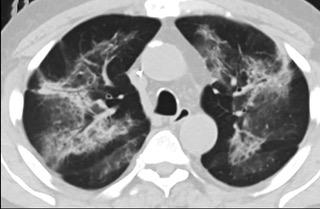

疑点一,电子烟患者的CT影像和临床表现并不具有特异性。所谓美国电子肺炎患者,其实是对没有其他合理诊断证据、吸食电子烟肺炎患者的统称。这些患者在病发前90天内吸食了电子烟,尤其值得注意的是,部分患者的CT影像特征和临床表现与病毒性肺炎患者极其相似。

中、下肺轴位CT平扫显示毛玻璃样混浊伴胸膜下保留。(同一病人CT影像)